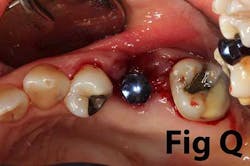

There is an abundance of literature showing increased gingival inflammation around natural dentition (exacerbated when a fixed restoration is present) when there is less than 2 mm AG. (Figs. 8, 9: post grafting) There is an abundance of literature showing increased incidence of peri-implant mucositis when there is inadequate attached tissue — a weaker connective tissue adhesion and lack of Sharpey’s fibers make the peri-implant tissue even more susceptible to bacterial challenge. (1-6, 8, 10) And as periodontitis is always preceded by gingivitis, peri-implantitis will be preceded by peri-implant mucositis. If we can decrease the incidence of peri-implant mucositis by providing a better and more resilient tissue phenotype, we can lower the incidence of peri-implantitis.The FGG procedure is indicated in cases of implant therapy where this is less than 2 mm of attached tissue present. Sometimes, a FGG is preferred over CTG because: (1) the FGG results in greater gain of attached tissue, (2) the FGG alleviates frenum/muscular pull whereas the connective tissue may increase muscular tension after the flap is coronally advanced, and (3) creeping attachment is often a positive byproduct of the FGG procedure.

Refer to Case Nos. 1 & 2.

Case No. 2